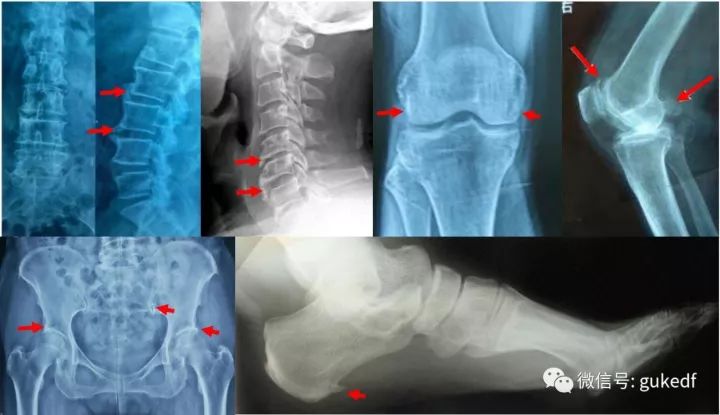

骨质增生最常见的部位是人体负重的大关节,尤其膝关节,其次是人体脊柱关节,尤其是颈腰椎,除此之外,还有负重的跟骨骨刺也非常常见。这些关节要么是活动度很大,要么就是负重很多的部位,也就是应力集中区域。因此这些区域最常发生骨质增生。

常见部位骨质增生X片